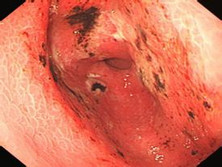

急性糜爛性胃炎是以胃黏膜多發(fā)性糜爛為特征的急性胃炎,又稱急性胃黏膜病變或急性糜爛出血性胃炎。近年來有上升趨勢,本病已成為上消化道出血的重要病因之一。

• 應(yīng)該做哪些檢查項目呢?胃鏡、X線平片